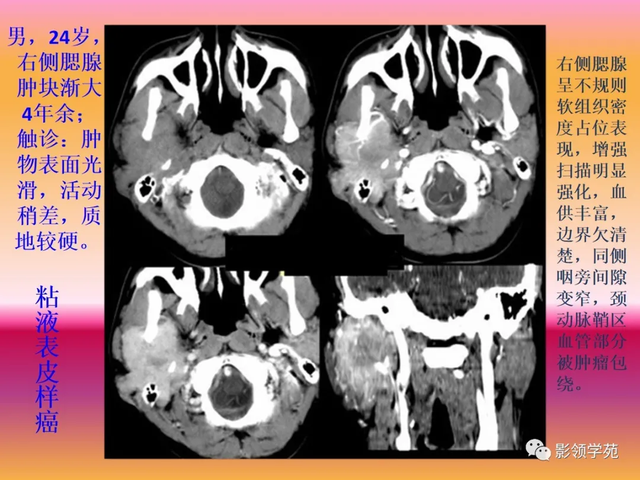

(1)腺泡细胞癌 2)粘液表皮样癌 3)腺样囊性癌

低度恶性:粘液表皮样癌,腺样囊性癌(圆柱癌);

多形性腺瘤(混淆瘤)

多形性腺癌(pleomrphicadenom)是一种包膜情形 纷歧,光镜下以结构多形性而不是细胞多形性为特征的肿瘤。通常上皮和变异肌上皮因素 与黏液、黏液样组织或软骨样组织混淆存在。曾以为 黏液软骨样组织来自间叶组织,故又称为混淆瘤(mixedtumor)。

多形性腺瘤是最常见的涎腺肿瘤,凭证 统计,多形性腺瘤占涎腺上皮性肿瘤的51%,占其良性肿瘤的88%。可发生于任何年岁 ,以30~60岁最多见,平均就诊年岁 是46岁。女性略多于男性。

约80%发生于腮腺,其次为下腺下腺,舌下腺有数 。

临床体现:

临床上通常体现为生长缓慢的肿块,巨细多数直径在2~5cm,也有长至很大者,肿瘤呈不规则形,外貌有结节,由于结构差异,触之软硬纷歧,可运动,发生于腭部和多次复发者一样平常 不运动,腭部肿物较大十黏膜外貌可形成创伤性溃疡。当生长加速并伴有疼痛时应思量 恶变。